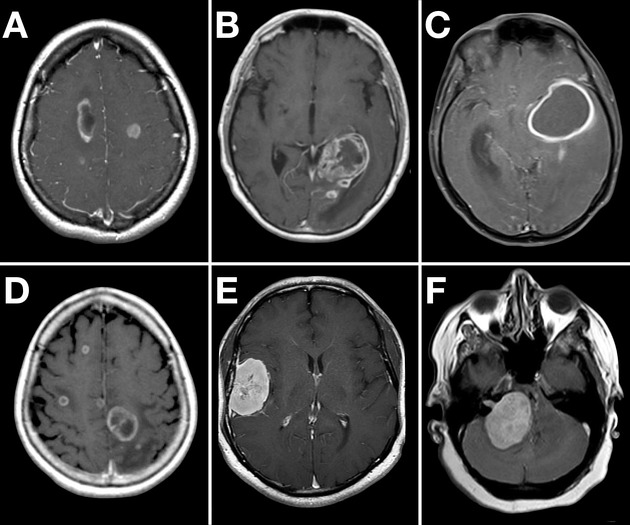

Example CT Images (Click to Enlarge)

| Space-occupying lesions (tumours, metastases) | Irregular or rounded mass, often with surrounding hypodense vasogenic oedema, variable contrast enhancement, and possible midline shift. |

| Brain abscess | Ring-enhancing lesion with surrounding oedema; often appears as a mass lesion with central low attenuation. MRI and clinical context help distinguish from tumour. |